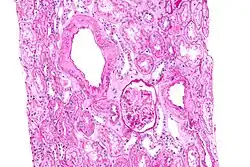

Amylose rénale

L’amylose rénale est de loin la plus précoce et la plus fréquente des complications

La substance amyloïde de la maladie périodique est formée de fibrilles identiques à la protéine de l'amylose AA, et elle intéresse de manière diffuse la paroi de toutes les artérioles, sauf celles du système nerveux central ; cette répartition est dominée par la localisation rénale..

La survenue d’une amylose au cours de la maladie périodique transforme une affection invalidante mais bénigne en une maladie mortelle quasi certaine. Son incidence est élevée chez les Juifs originaires d’Afrique du Nord et chez les Turcs et plus faible chez les Arméniens, les Arabes et les Juifs ashkénazes[1].

Son évolution passe par deux phases principales. Le début est asymptomatique, il s'agit d'une protéinurie modérée, de durée moyenne de 3 à 4 ans. Son apparition au cours de la maladie périodique constitue une très forte présomption d’amylose, et cette protéinurie doit être recherchée au moins une fois par an[31].

La phase néphrotique est caractérisée par l’apparition d’un syndrome néphrotique clinique et biologique. La confirmation histologique peut être apportée par la biopsie rénale, la biopsie rectale (positive dans 75 à 85 % des cas), voire par la biopsie médullaire.